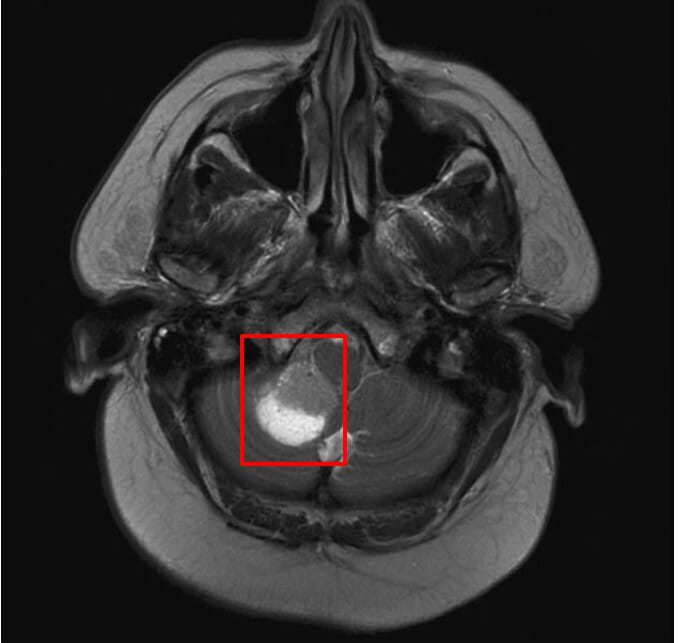

뇌 MRI 소견

소세포폐암은 뇌 전이가 흔합니다. 뇌 전이 병변 영상 소견을 정리해보겠습니다.

| 다발성 조영 증강 병변 |

| 회백질 경계(gray-white junction)에 전형적인 뇌 전이 병변이 관찰됨 |

| 무증상 뇌 전이 |

| 초기에는 무증상이나 영상에서만 확인되는 경우 많아 예방적 방사선 치료 고려 |

Gaillard F, Cerebellar metastasis – small cell lung cancer. Case study, Radiopaedia.org (Accessed on 20 Apr 2025) https://doi.org/10.53347/rID-10248